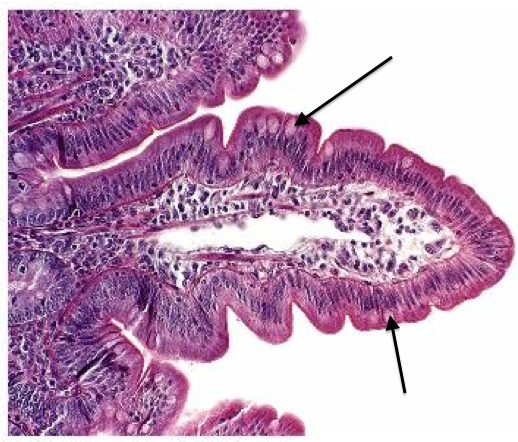

Name this tissue and epithelium which lines it

Large intestine - columnar epithelium

206

Goblet cells

207

Lamina propria

208

Crypts of Lieberkuhn